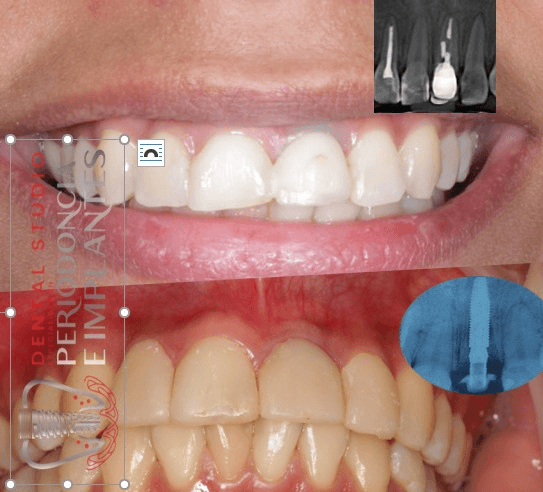

Implante Inmediato pos exodoncia de diente fracturado (central superior izquierdo)

Paciente con fractura del central superio izquierdo; se le realiza la exodoncia mínimamente traumática, posterior a ello se coloca un implante con la asistencia de una guía quirúrgica y se realiza carga inmediata sin contacto oclusal.